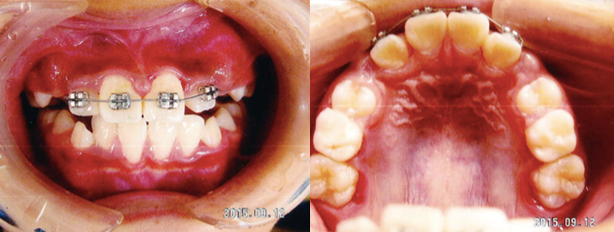

八重歯・乱ぐい歯(叢生)

八重歯の原因は、顎のスペースが足りないために起こります。スペースがないところに

歯が生えてくると歯並びがガタガタになります。そのため虫歯や歯周病のリスクが高くなります。

ケース1

治療前

治療後